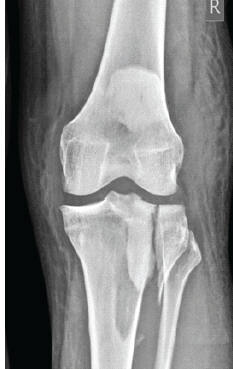

Functional Outcomes and Surgical Utility of the Modified Schatzker Four-column Concept in Proximal Tibial Plateau Fractures: A Prospective Observational Study

Sreekanth Kashayi-Chowdojirao , K K Kiran Kumar , Pankaj Kabra , K Joy , Safia Sultana